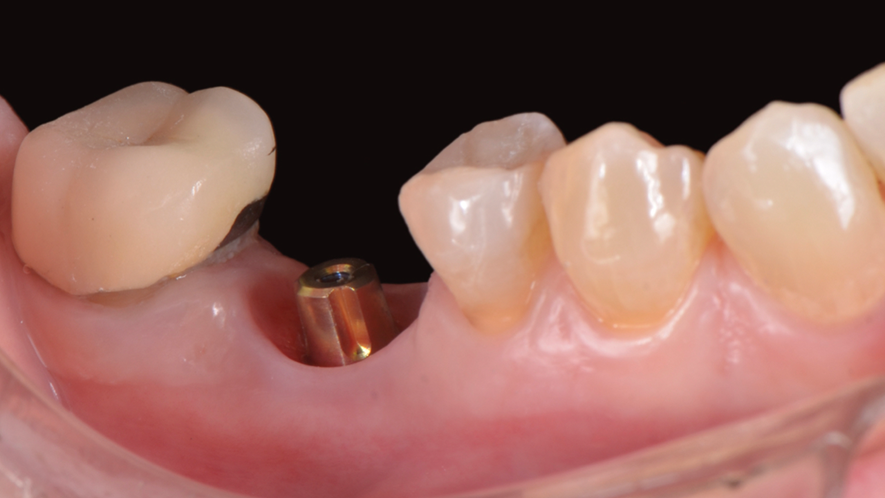

Iniciamos o planejamento com o escaneamento intraoral e uma tomografia computadorizada cone beam da mandíbula. De posse das informações, foi realizado o planejamento virtual do implante no Exoplan (Exocad) e o desenho e impressão da guia cirúrgica, bem como de uma coroa provisória CAD/CAM. A cirurgia guiada foi realizada com o Kit Implaguide CM 3.5, seguindo a sequência de fresas preconizadas pela Implacil De Bortoli. Foi instalado o implante Maestro de 3,5x11mm (Figura 1) e, logo após, o pilar Ideale 4,5x4x2,5. A coroa provisória CAD/CAM foi capturada utilizado a coifa provisória de titânio do pilar ideale(Figura 2). Após 60 dias de pós-operatório, a coroa provisória foi removida e observada em excelente perfil de emergência (Figura 3). Solicitamos uma nova tomografia e começamos a planejar a coroa definitiva, num fluxo restaurativo 100% digital com o iTero.